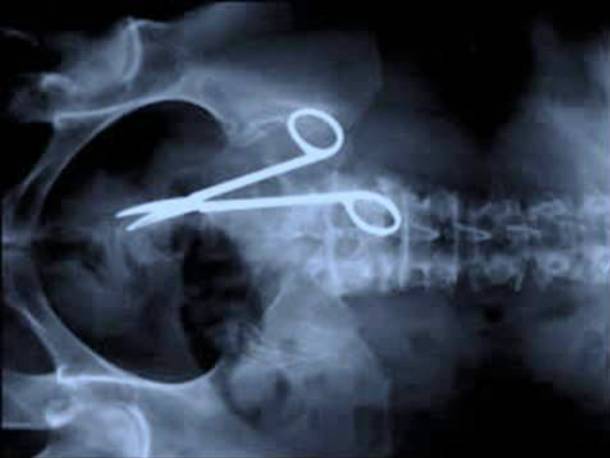

7. Scissors In The Stomach

We can't imagine the kind of stomach pain that scissors would cause. But this is what happened to Australian Pat Skinner, he came back to the hospital 18 months after surgery complaining of stomach pain. It seems that the doctors had forgotten their surgical scissors...inside of him.Advertisement